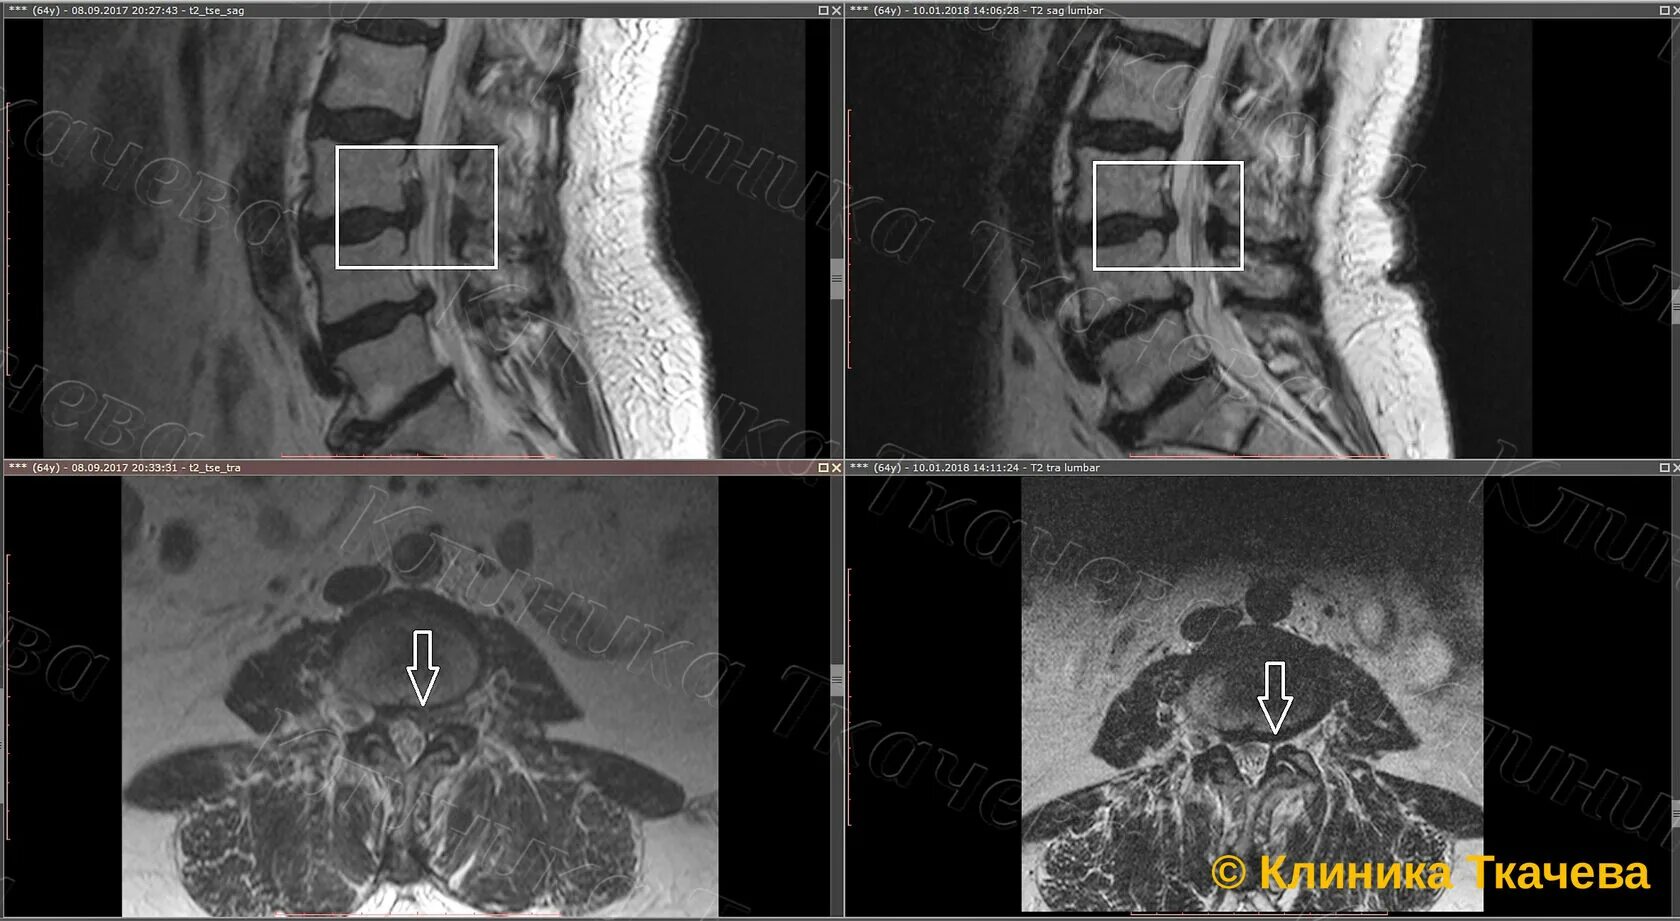

Каудальная миграция грыжи диска